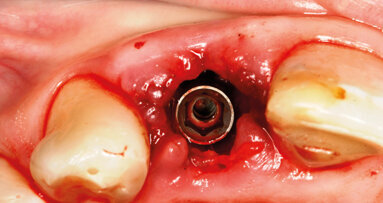

È sempre più attuale e dibattuta dalla comunità scientifica la sostituzione di elementi in zona estetica con impianti ...